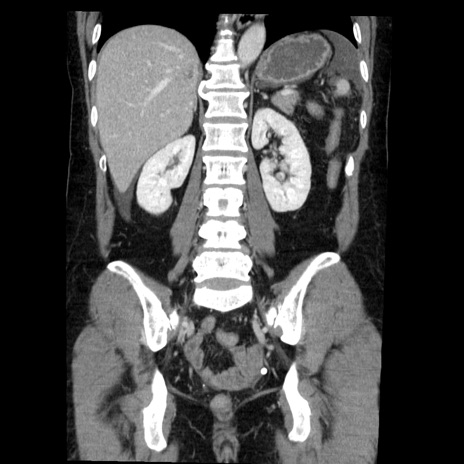

症例6(冠状断像)

【症例】50歳代女性

【主訴】下腹部痛

【現病歴】本日朝より下痢2回あり。 昼食を食べた後、嘔吐3回、下腹部痛認め、症状軽快せず、当院救急搬送。

最終食事:本日昼(生ものなし)。 昨日の夜、刺身を食ぺたとのこと。周囲に同様の症状の者なし。普段、排便は毎日あるとのこと。

【既往歴】卵巣癌術後(8年前に当院で卵巣摘出)

【身体所見】 意識清明、腹部:平坦、腸蠕動音→、やや硬、下腹部自発痛・圧痛あり、反跳痛あり、筋性防御なし。

【データ】WBC 16000、CRP 0.01